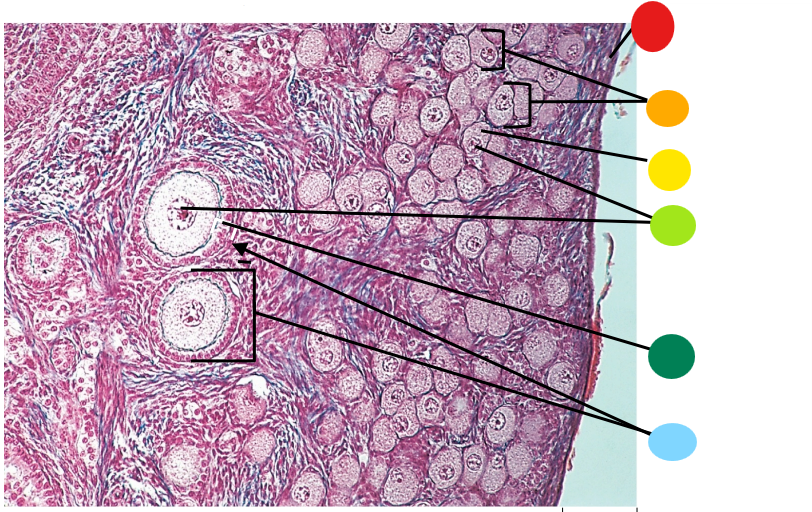

red

tunica albuginea

orange

primordial follicles

yellow

follicular cells

light green

primary oocyte

dark green

granulosa cells

light blue

primary follicles

what is this?

ovary